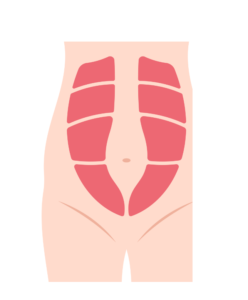

DRAM ( Diastasis)

DRAM (Diastasis Recti Abdominis Muscles), is separation of the connective tissue between the rectus abdominis, becomes stretched and weakened.

DRAM (Diastasis Recti Abdominis Muscles), is separation of the connective tissue between the rectus abdominis, becomes stretched and weakened.

it can cause visible bulging or Pooch in the abdomen, often seen when you engage your abdominal muscles, especially when you are sitting up or standing.

It can appear as a bulge or ridge running down the middle of the abdomen.

Generally, the width of the gap decreases with recovery from the delivery

If size of the DRAM is severe, it can cause

- Weakness of core & Lower back pain

- Poor posture

- Pelvic Floor dysfunction

- Difficulties of Physical activities which requires core strength